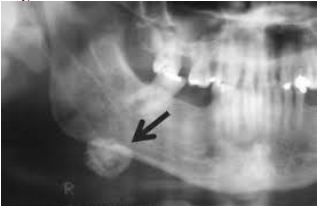

Paciente T.F., 42 anos, melanoderma, sexo masculino, compareceu à clínica odontológica após queda de bicicleta. Ao exame clínico, você observa edema na região inferior da mandíbula. O paciente relata desconforto local e dor. Suspeitando de fratura, você solicita uma radiografia panorâmica. Ao examinar a radiografia, nota-se uma imagem radiopaca na porção inferior da mandíbula, próxima à região de ângulo mandibular. Notadamente, a imagem radiopaca ocorre em tecido mole.

Nesse contexto, você tem como diagnóstico:

Fonte: Ramos-Jorge, Motta-Rêgo e Santos (2006)